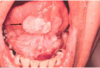

Erythematous

Candidiasis

what are its

Clinical finding?

Subtypes?

● Clinical Findings:

- Red macules or patches

- Can be due to multiple things

● Subtypes:

‐ Atrophic Candidiasis (acute‐feels like mouth has been scalded)

‐ Median Rhomboid Glossitis (asymptomatic)

‐ Denture Stomatitis (asymptomatic)

■ HAS THE SHAPE OF THE DENTURE

‐ Chronic multifocal (asymptomatic)

■ THIS HAS BEEN THERE FOR A LONG TIME